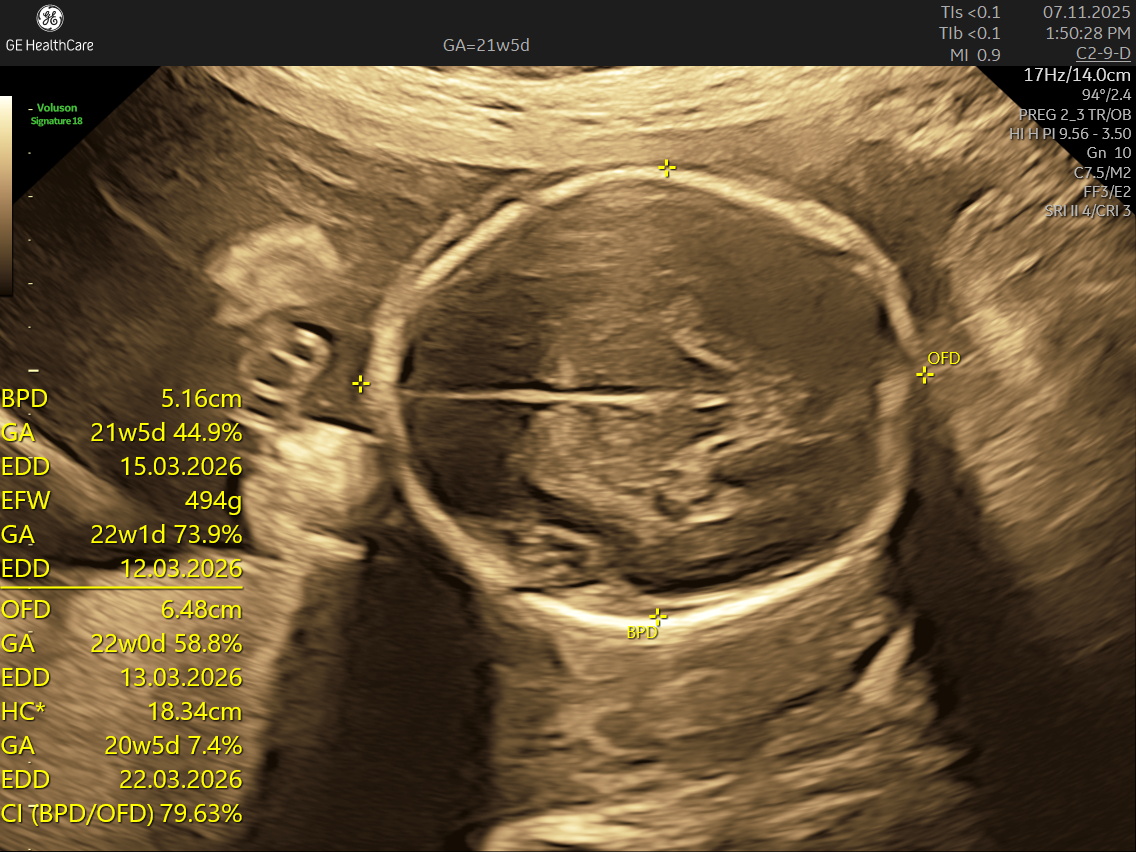

If you’re expecting a baby, the Detailed Anatomy Scan —also known as the Fetal Anomaly Scan — is one of the most important checks you’ll have during pregnancy. Usually done between 18 and 22 weeks, this ultrasound is performed by highly trained fetal medicine specialists at NESA Institute of Fetal Medicine. The scan provides a close-up look at your baby’s overall development and helps to make sure everything is progressing as it should.

During this scan, the MFM specialist carries out a detailed examination of your baby’s body, checking their vital organs, spine, head, heart, limbs, and more. The aim is to confirm that your baby’s growth is on track and can identify various structural abnormalities and potential complications early, so that appropriate steps can be taken early.

• Head and Brain: The scan looks at the baby’s skull shape and examines the brain’s key areas, checks the structure and growth of the brain and skull, ensuring everything is forming correctly.

The anatomy (anomaly) scan is a vital prenatal ultrasound performed around 18-22 weeks of pregnancy to thoroughly examine the developing fetus's organs, body structures, placenta, and amniotic fluid. It helps detect major congenital abnormalities such as neural tube defects, heart anomalies, facial clefts, and abdominal wall defects, providing crucial information for medical management and parental preparation. While not 100% definitive, it is highly accurate and safe, offering reassurance when normal and timely intervention options if issues are found. Proper timing, preparation, and specialized follow-up care enhance the scan's benefits. This scan empowers expectant parents and healthcare providers with knowledge that supports healthy pregnancy outcomes and informed decision-making. It remains one of the most important screenings in prenatal care today